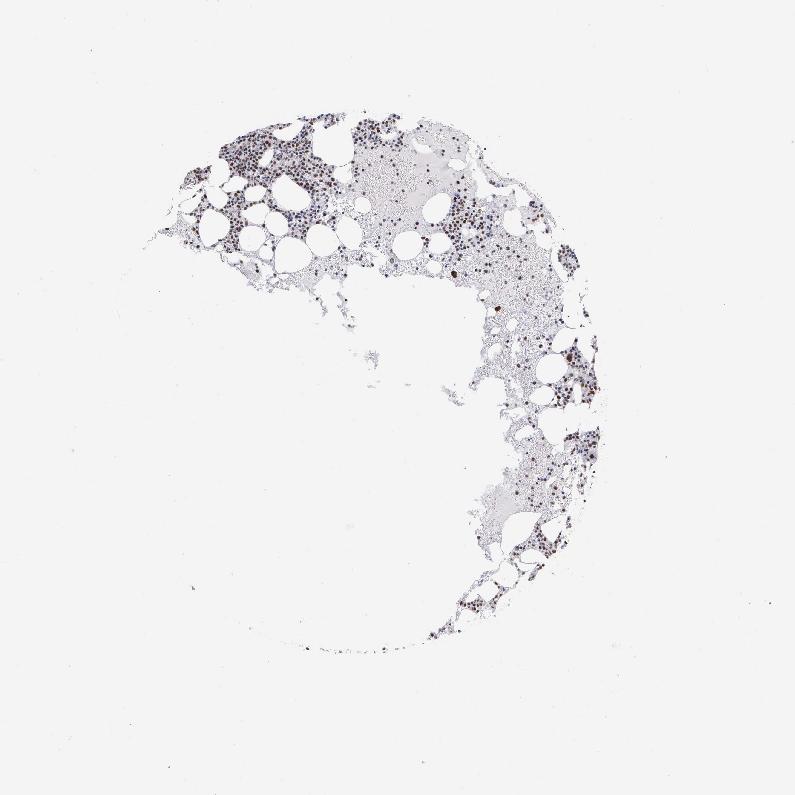

TISSUE PRIMARY DATA BONE MARROW Show tissue menu

BONE MARROW - Antibody stainingi

Antibody staining in the annotated cell types in the current human tissue is reported as not detected, low, medium, or high, based on conventional immunohistochemistry profiling in selected tissues. This score is based on the combination of the staining intensity and fraction of stained cells.

Each image is clickable and will lead to virtual microscopy that enables deeper exploration of all samples and also displays staining intensity scores, fraction scores and subcellular localization as well as patient and tissue information for each sample.

Antibody HPA000427Antibody CAB004680

Hematopoietic cells HighLow